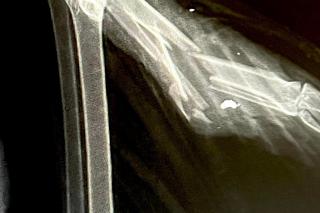

Na Podkarpaciu ktoś strzela do bocianów jak do żywych tarcz. W ostatnich dniach do Fundacji Ada w Przemyślu trafiło kilkanaście ptaków z ranami postrzałowymi. Jednego nie udało się uratować, był postrzelony aż 12 razy! Śrut zniszczył jego wątrobę, płuco, skrzydło i miednicę. Postrzelony bocian zazwyczaj kończy jako kaleki ptak, który już do końca życia nie będzie mógł żyć na wolności. Wszystkiemu winien jest człowiek.

- Ktoś sobie z tego bociana po prostu zrobił żywą tarczę. Miał w ciele mnóstwo śrutów, mnóstwo złamań. Niektóre były w okolicach płuc, serca - zaznacza lekarz weterynarii Angelika Szkolnik.